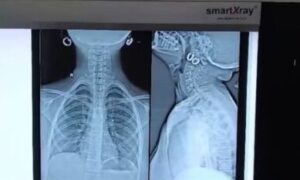

વડોદરા SSG હોસ્પિટલના તબીબોની કમાલ: 13 વર્ષની બાળકીના ગળામાં ફસાયેલી પિન સફળ ઓપરેશન દ્વારા બહાર કઢાઈ